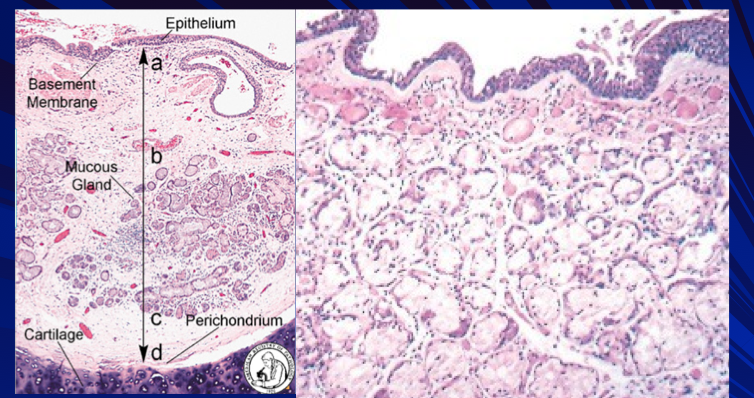

Describe the pathophysiology behind chronic bronchitis

Hypertrophy of bronchial mucinous glands

Reid index (thickness of mucosal gland layer relative to bronchial wall thickness) >50%